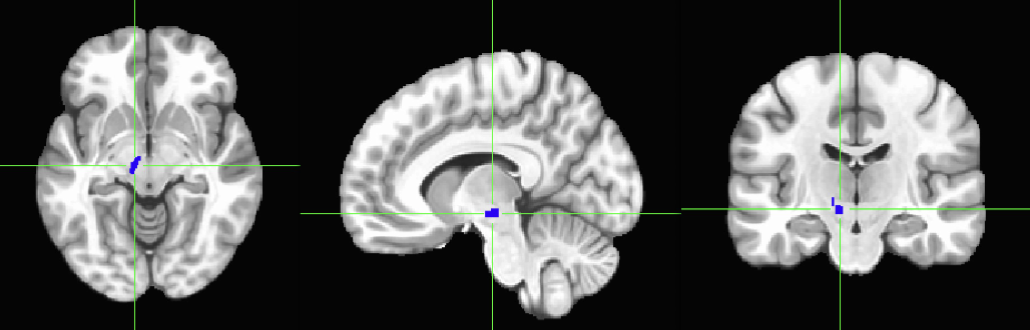

SUBSTANTIA NIGRA– This is the left hemisphere, we have a

right SN as well. Both, left and right, are important

synthesizers of Dopamine. The other important synthesizer of

DA in the brain is the VTA, which is next to the SN.